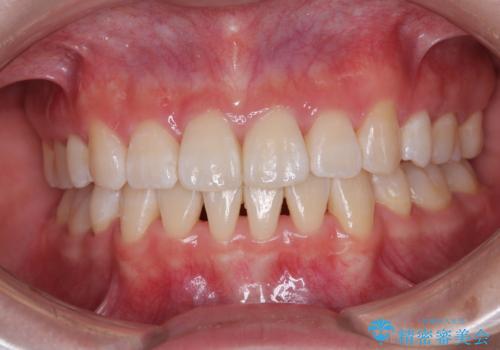

- 急速拡大装置 狭い骨幅を拡大した上で、口元の突出感を改善する抜歯矯正治療

- 【モニター】とがった口元を抜歯して改善 ワイヤー装置の矯正治療- 担当医 藤巻太一朗

- 出っ歯を治したい ワイヤー装置での抜歯矯正- 担当医 藤巻太一朗